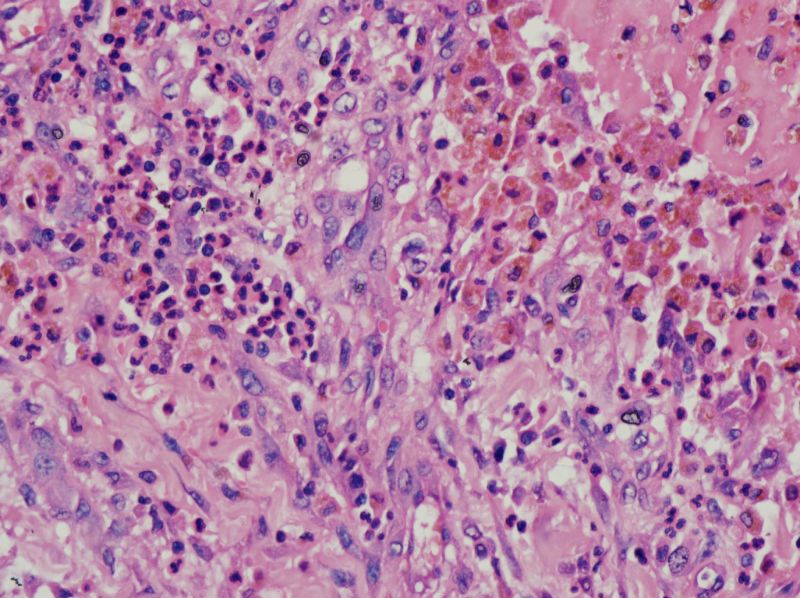

• 甲状腺囊肿,请老师们指教图2

图2

结节性甲状腺肿伴出血、囊性变。囊肿边上的滤泡大小不一,纤维组织增生,还可见炎细胞浸润。